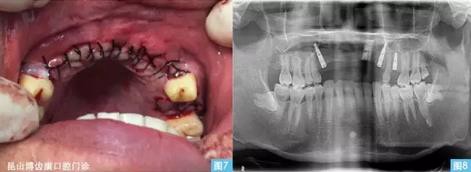

圖7圖8:(左圖7)黏膜對(duì)位縫合,(右圖8)種植術(shù)后曲面體層攝影。